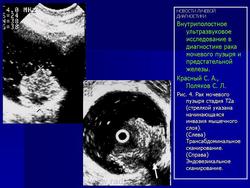

На Рис. 4 представлены эхограммы одного больного - трансабдоминальное и эндовезикальное исследование. Трансабдоминальное сканирование в данном случае не позволяет судить о глубине инвазии, а при эндовезикальном исследовании выявлена начинающаяся инвазия мышечного слоя, причем место инвазии визуализируется как гипоэхогенный участок на фоне гиперэхогенной мышечной ткани (стадия Т2а). Более четко визуализируется инвазия глубокого мышечного слоя (стадия Т2в) (Рис. 5).